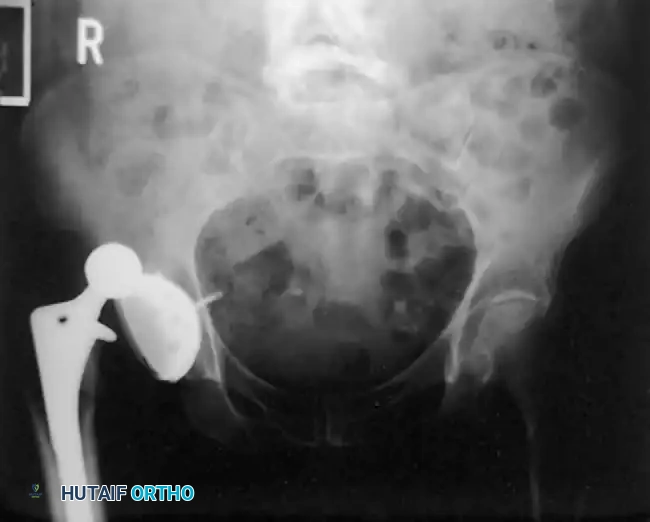

Associated Surgical & Radiographic Imaging